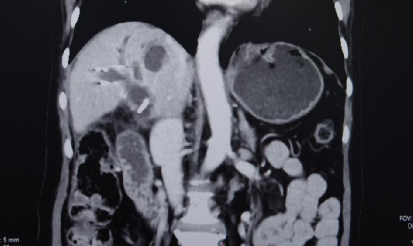

CT(2025.2.18):1、肝右叶异常强化团块影伴周围胆管扩张,考虑肝内胆管癌可能性大,门静脉右支充盈缺损影,考虑癌栓形成。2、脾脏缺如;胆囊、胰腺、双肾及双侧肾上腺未见明显异常

TACE术后28天影像学检查

与2025-02-18日腹部增强片对比示:1.肝右叶多发低密度结节,考虑胆管癌,最大病变内多发颗粒状致密影,考虑介入术后改变,较前病变内坏死增多。肝中静脉局部走行于病灶边缘,管腔未见明显受侵。2.门脉右支起始处少许癌栓,远端未见显影,考虑治疗后改变。3.脾脏缺如;胆囊继发性改变,胆囊窝积液。肠系膜间可见多发稍大淋巴结。